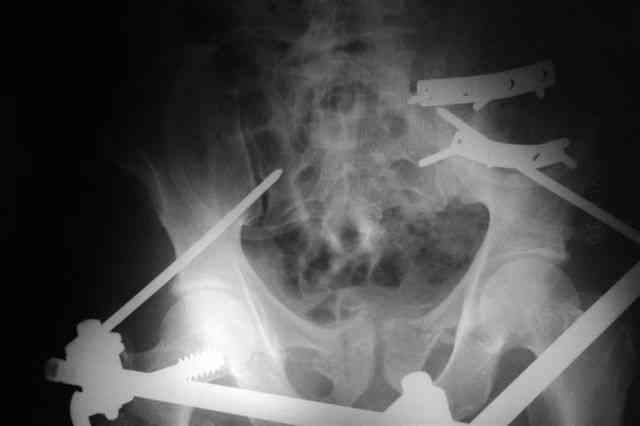

Я помню технику транссакральной фиксации тазового кольца длинными 5 мм Шанцами - повреждения типа В, в этом же случае задний отдел тоже вовлечен

т.е комбинированная нестабильность, поэтому вопрос - достаточно ли только двух Шанцев для стабилизации таза? Что вы думаете об anterior Right SI joint plating + tension band plating from the back.?

PS после фиксации бедра под Эопом посмотрел инлет и аутлет проекции, насколько репонируемо смещение правой половины таза *невооруженными*

руками - никаких шансов улучшить позицию иначе бы конечно воспользовался длинными Шанцами сразу после бедра.

Элегантная фиксация, поздравляю.Но ваш случай : одноплоскостная горизонтальная нестабильность Tyle B2.2 отличен от представленного мной - у

моего больного + вертикальная нестабильность за счет повреждения правого крестцово-подвздошного сочленения и перелома заднего отдела подвздошной

кости- С2 тип. Поэтому и возникла дилемма : выбор оптимальной фиксации заднего отдела:

По-поводу фиксации таза спонгиозными винтами. Данный способ все-таки показан для фиксации повреждения крестцово-подвздошного сочленения или переломов крестца. Мне кажется, что в данной случае ситуация иная - имеется перелом "основания" крыла подвздошной кости (в который вовлечена и поверхность, составляющая крестцово-подвздошное сочленение). Не уверен, что фиксация данного повреждения (и заднего полукольца) винтами будет стабильной, так как именно на уровне 1-2 крестцовых позвонков (где обычно вводят винты) линия перелома уходит в латеральном направлении от крестцово-подвздошного сочленения.

По-поводу репозиции костей таза. Производить репозицию костей все-таки необходимо. Пока я не встретил информации, сколько времени прошло с момента травмы, но одномоментно низвести правую половину таза может быть тяжело, учитывая и наличие перелома бедренной кости (что затруднит тракцию за нижние конечности).

Я просмотрел томограммы и у меня создалось впечатление, что винтам есть за что *зацепиться*. В сочетании с 5 мм Шанц винтами, проведенными через нижне-переднюю ость спереди назад через КП сочленения -стабильность тазового кольца должна восстановиться. - Это , конечно, при условии , что закрытая рнепозиция будет успешной.

Травма произошла 22 или 23 декабря, ко мне больной попал 26 декабря, 3 января -остеосинтез перелома бедра и внутр.лодыжки.